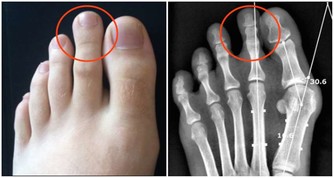

期間,身體的纖維細胞大量製造膠原收復皮膚, 正常的一般皮膚傷口會在一至兩星期內癒合,

經過結痂及表皮再生過程後,大約十天即會長出新皮,期間皮膚傷口附近會紅腫,麻痺和癢。

由於多了血液,膠原及組織液於傷口附近進行上面的過程, 壓力會刺激附近的神經線,

造成紅腫,麻痺和癢甚至脹痛!